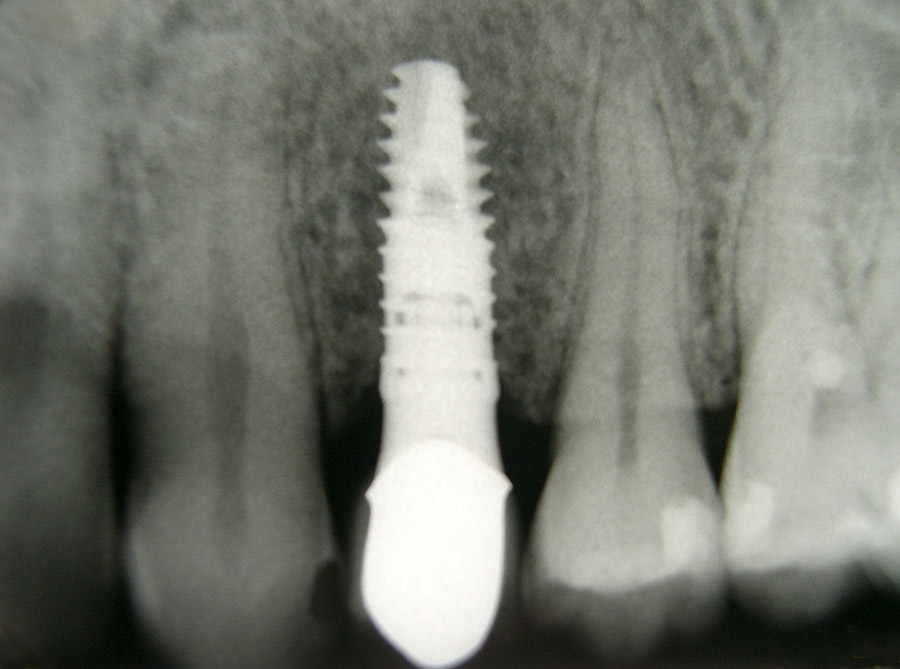

Zahnimplantate bieten heute eine bewährte und zuverlässige Möglichkeit, verloren gegangene Zähne zu ersetzen. Sie übernehmen die Aufgabe der natürlichen Zahnwurzel und tragen so einzelne oder auch mehrere fehlende Zähne.

Ein besonderer positiver Effekt der Implantate ist, dass sie den Kieferknochen und das Zahnfleisch erhalten, während sich der Knochen unter Brücken und Prothesen hingegen abbaut. In vielen Fällen lässt sich so die natürliche Rot-Weiß-Ästhetik, also das harmonische Zusammenspiel von Zahnfleisch und Zähnen erhalten, so dass implantat-getragene Kronen kaum von eigenen gesunden Zähnen zu unterscheiden sind.